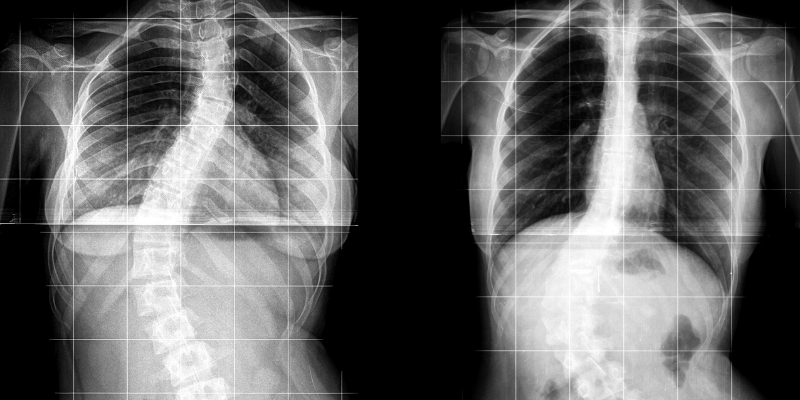

spinal fusion operation rscoliosis

spinal fusion rscoliosis 640×640 spinal fusion rscoliosis from www.reddit.com